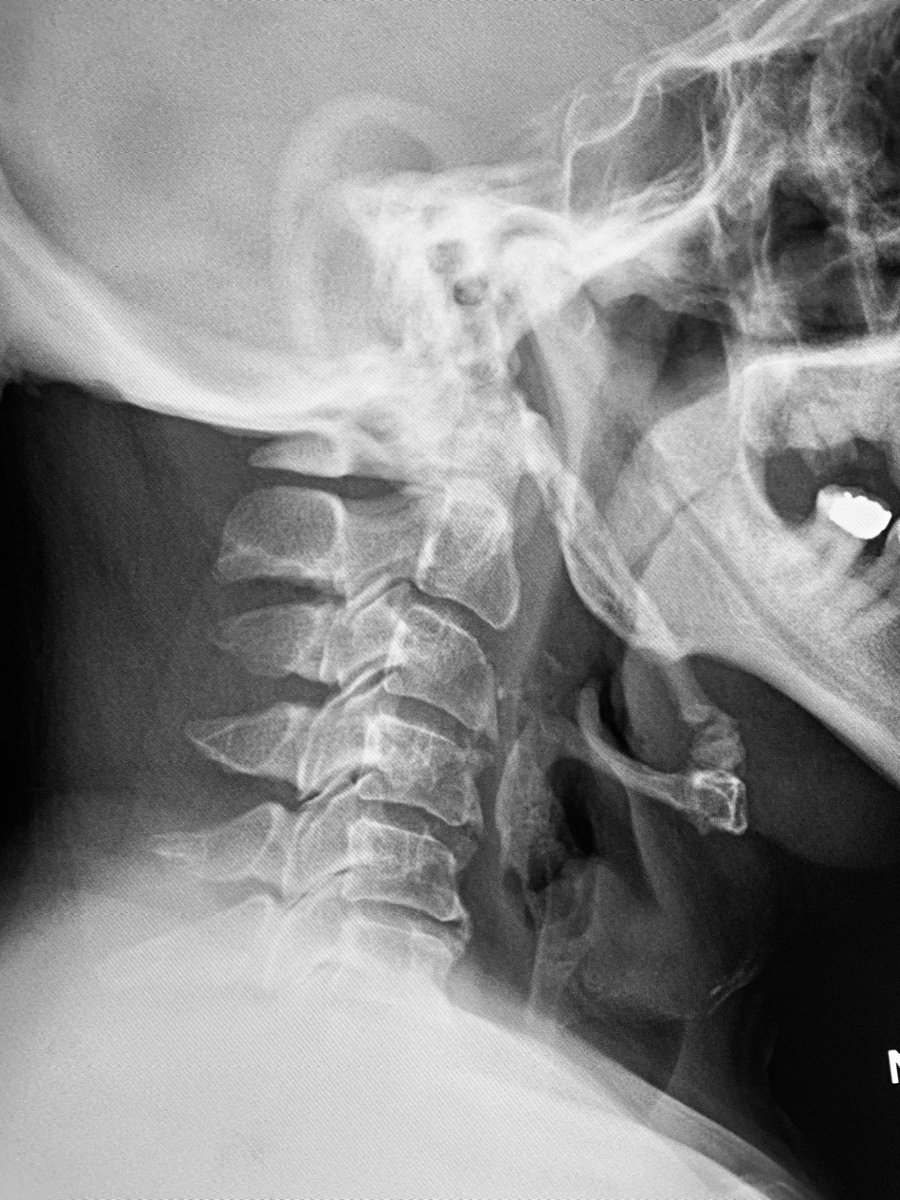

One of the largest malpractice awards ever just dropped: "Hospital on the hook for $120M jury verdict after residents miss signs of stroke on CT" radiologybusiness.com/topics/healthc… Always interested in learning from diagnostic error, I looked up the court documents.🧵pt1 (names redacted)